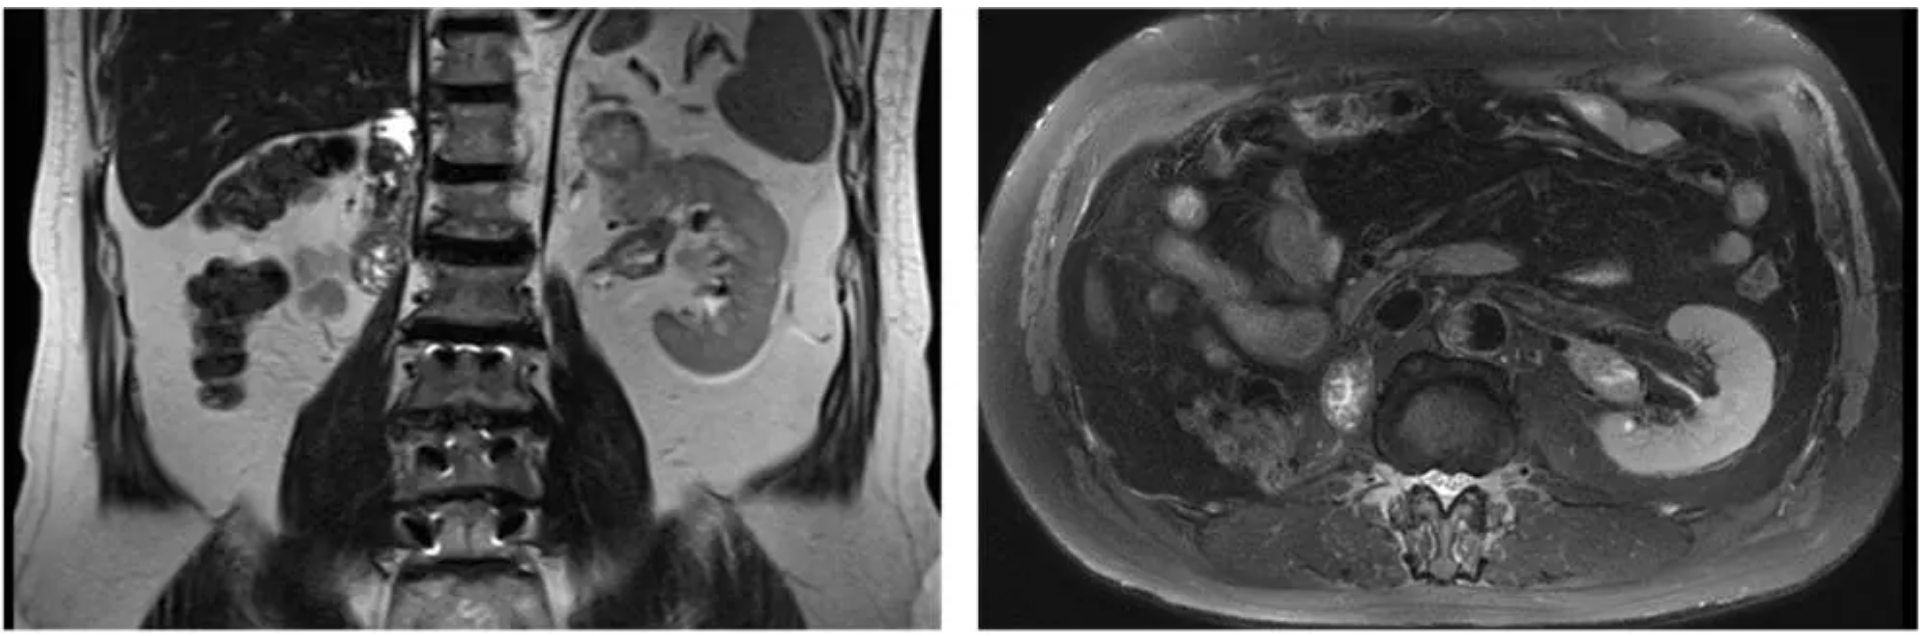

Until June this year, his kidney "broke down" again: a tumor was detected in his precious solitary left kidney, and this time, the tumor had invaded the renal vein. The result was a bolt from the blue for Mr. Zhang. To save this kidney, he visited major urological centers across the country, but all proposed radical nephrectomy followed by regular hemodialysis.

After this consultation, Mr. Zhang regained confidence. After five courses of targeted combined immunotherapy as neoadjuvant treatment, the tumor and renal vein thrombus shrank, with serum creatinine maintaining around 140 μmol/L. When all preparations were complete, he returned to Renji.